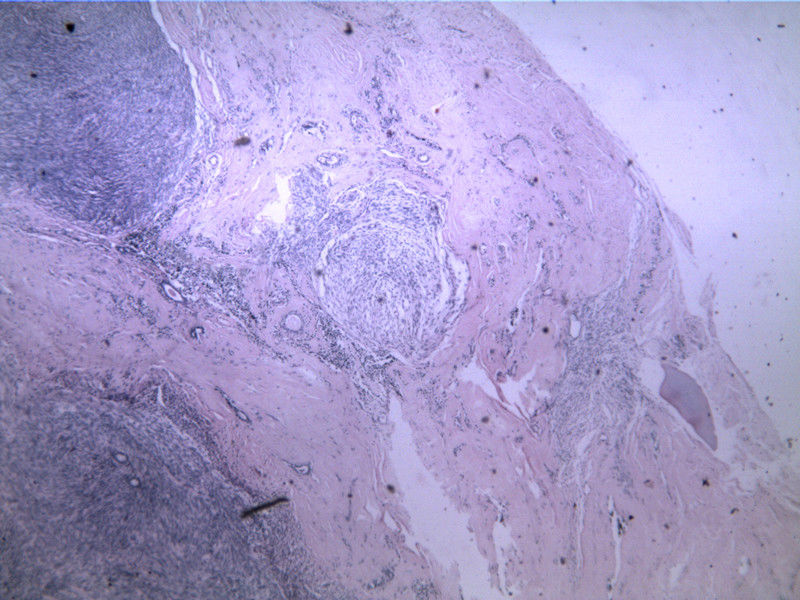

B3817

包块-有包膜(V3x3x2,39y)

图1

叶状肿瘤 导管周间质肿瘤